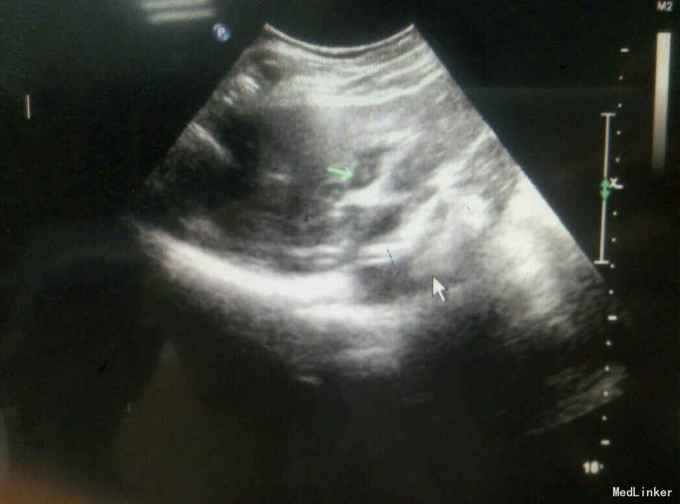

患者,女,45岁,发现左乳肿物半年余

查体:左乳外上可及一大小约为5cm肿物,质硬,边界欠清 辅查:

诊断:左乳癌?左乳纤维腺瘤?肉瘤? 治疗:患者入院后于局麻下行左乳肿物穿刺活检术,术后病理提示:左乳恶性肿瘤,肉瘤待排,遂全麻下行左乳癌改良根治术加腋窝淋巴结清扫术,术后病理示:左乳恶性肿瘤,考虑骨肉瘤可能性大,淋巴结未见转移。